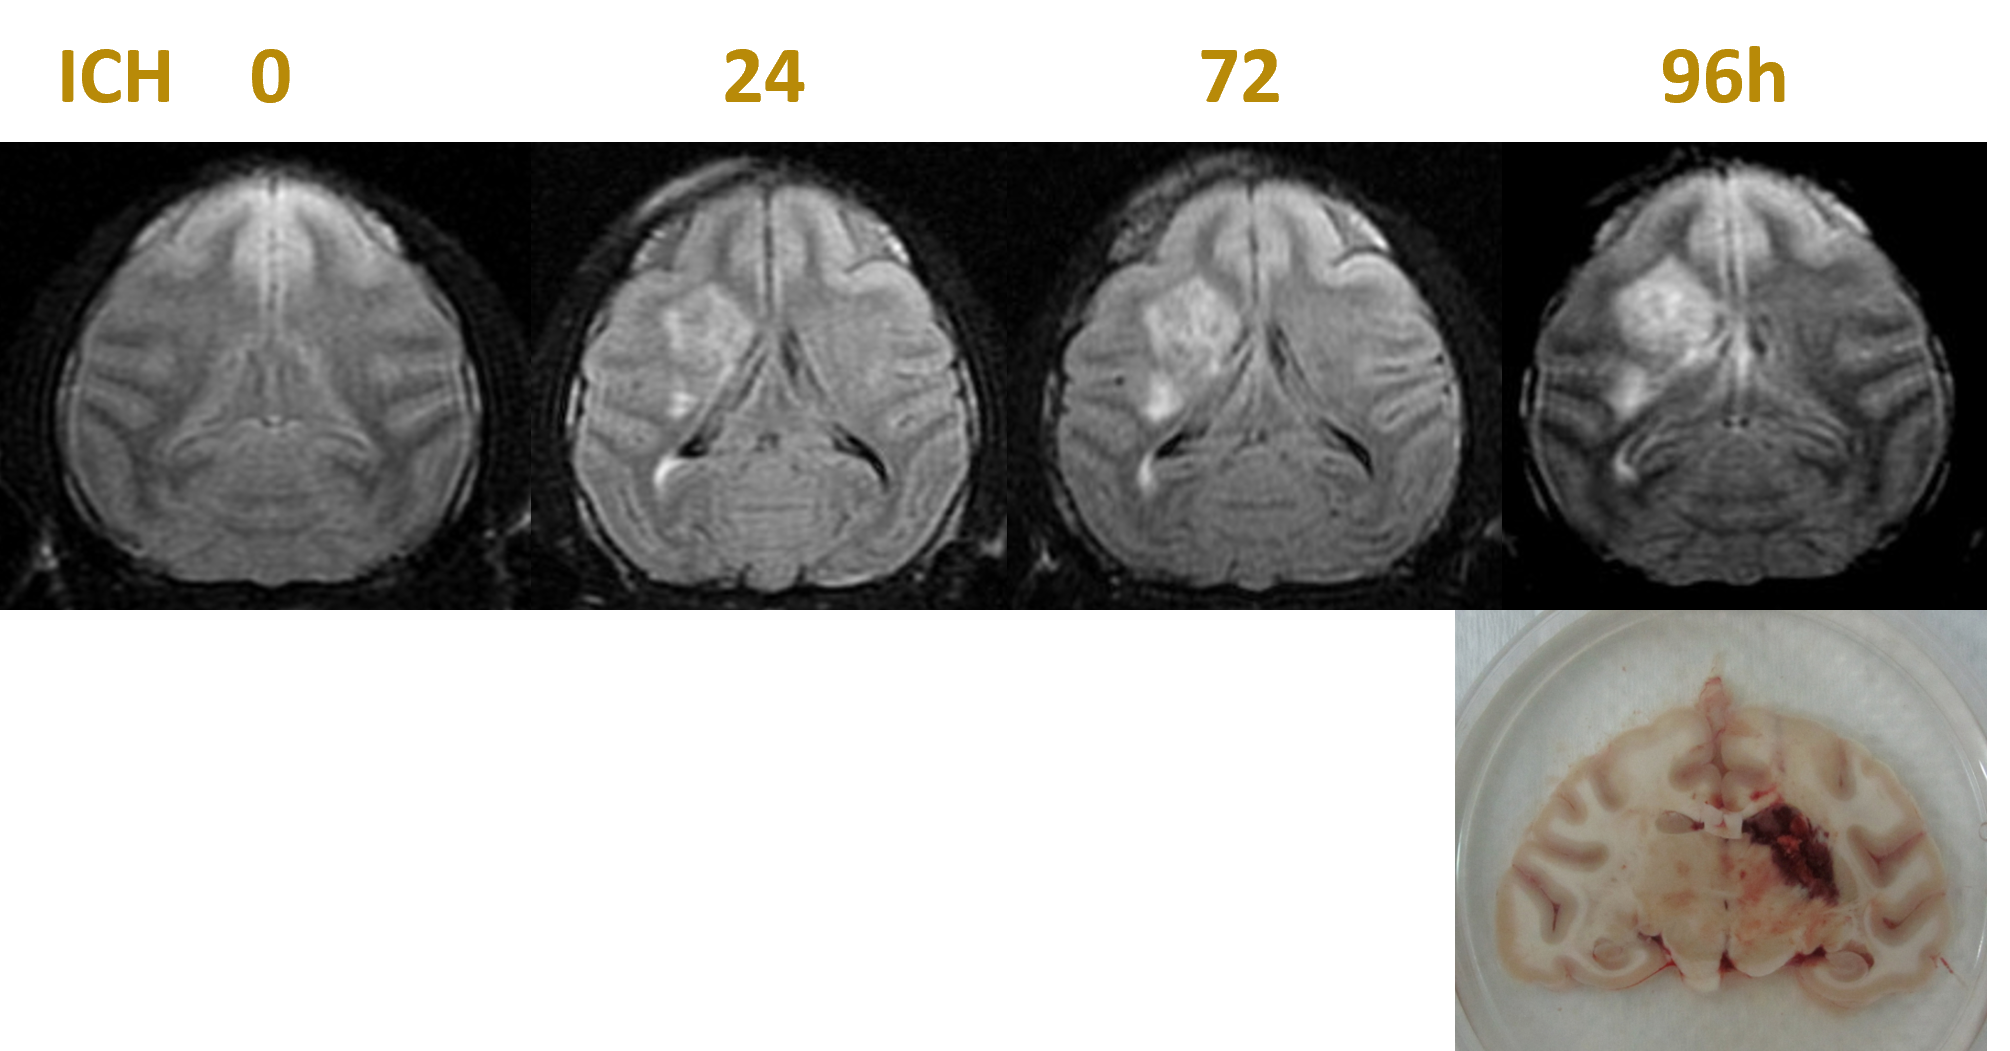

▲Stroke ▲Sleep disturbance ▲Dementia ▲Parkinson's disease ▲Pain models |